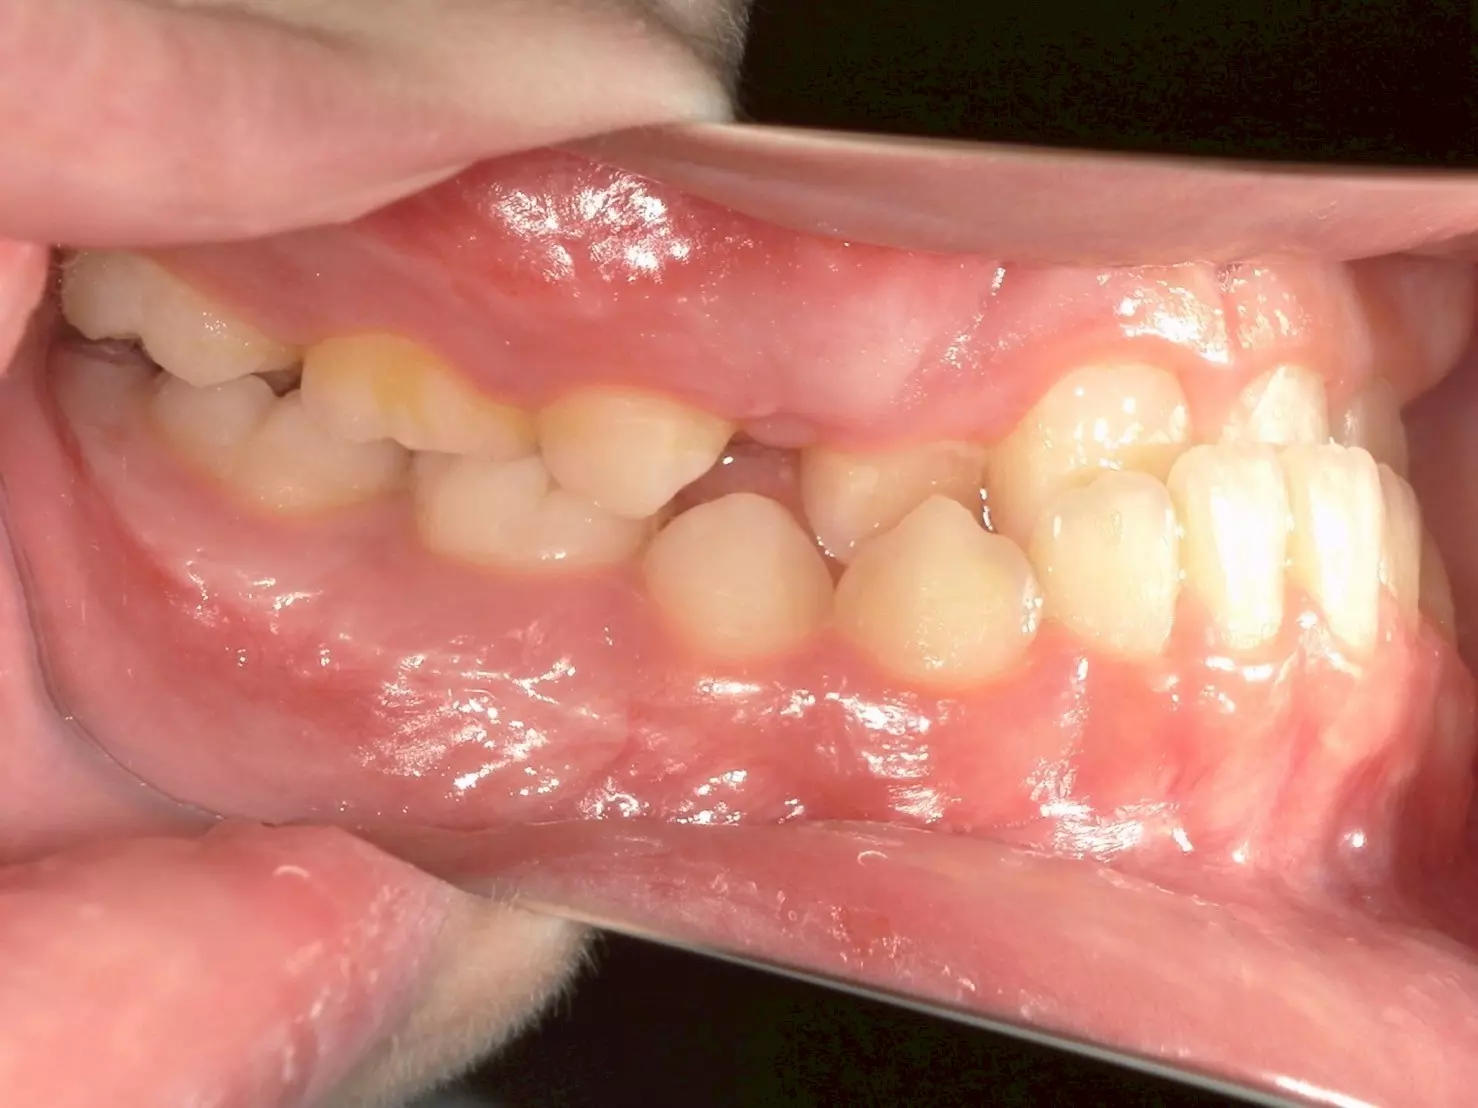

這位 11 歲的男孩,因為前牙錯咬問題導致上顎的牙弓變窄,前牙空間不足,不僅影響到進食,連笑容都變得不自然。他的父母觀察到,孩子不太喜歡吃東西,也漸漸在笑的時候變得保守,甚至開始避免拍照。

經過仔細檢查後,我們確認他屬於功能型第三類咬合異常 (Functional Class III)。這和大家熟知的「骨性戽斗」不同,他的狀況主要是因為牙齒排列影響了上顎的發育。這類型的咬合異常,如果沒有及早治療,可能會影響上顎的生長空間,進而讓整體顏面外觀及咬合狀態惡化。

↑治療前